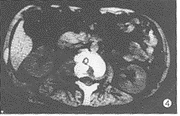

图4 腰1椎体结核骨质破坏并右侧腰大肌冷脓肿